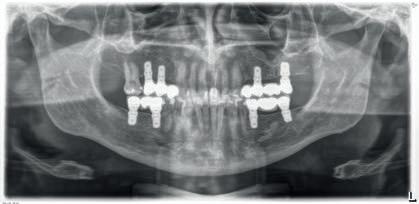

A PROPÓSITO DE UN CASO Paciente hombre de 52 años de edad que acude a la consulta demandando tratamiento implantológico para varias ausencias dentales y la restauración de los dientes remanentes (Figuras 1 y 2). El caso fue estudiado mediante modelos diagnósticos, exploración clínica y radiográfica.

Figura 2. Imagen radiográfica de diagnóstico inicial mostrando la ausencia de piezas dentales en los sectores posteriores, la presencia de diferentes grados de desgastes dentales y raíces dentales remanentes. También muestra la presencia de varias lesiones periapicales.